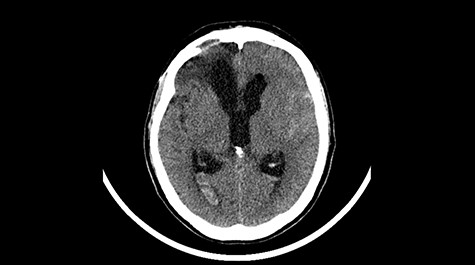

Head CT after polypectomy—seen defects of the upper left orbital wall. (Department of Neurosurgery own material).

In described case, a head CT scan after polypectomy confirmed the subarachnoid hemorrhage (Fig. 1). In addition, the presence of air in the ventricular system was visible, and presence of defects of the upper left orbital wall and ethmoid on both sides (Fig. 3). In the CT scan sphenoid sinus, frontal and ethmoidal sinuses on both sides and right maxillary sinus airless, filled with blood and soft tissue. The changes also concerned the lateral part of the left maxillary sinus (Fig. 4).

The present bone defects were most probably caused by the development of osteomalytic foci as a consequence of the spread of the inflammatory process within the diploe of flat skeletal skull bones, in the course of chronic rhinosinusitis. Both underestimating the severity of complaints in the course of chronic rhinosinusitis and delaying the implementation of surgical treatment led to massive bone destruction, which had an impact on the development of further complications after polypectomy (including subarachnoid hemorrhage). Performed angio-CT excluded any malformations and the probable cause of subarachnoid hemorrhage due to rupture of the aneurysm. Considering the radiological picture and the condition of the patient, it can be concluded that the persistent inflammatory process within sinuses led to dehsomination and subsequent bleeding into the subarachnoid space through discontinuity in the bone structure of the sinuses and orbits.